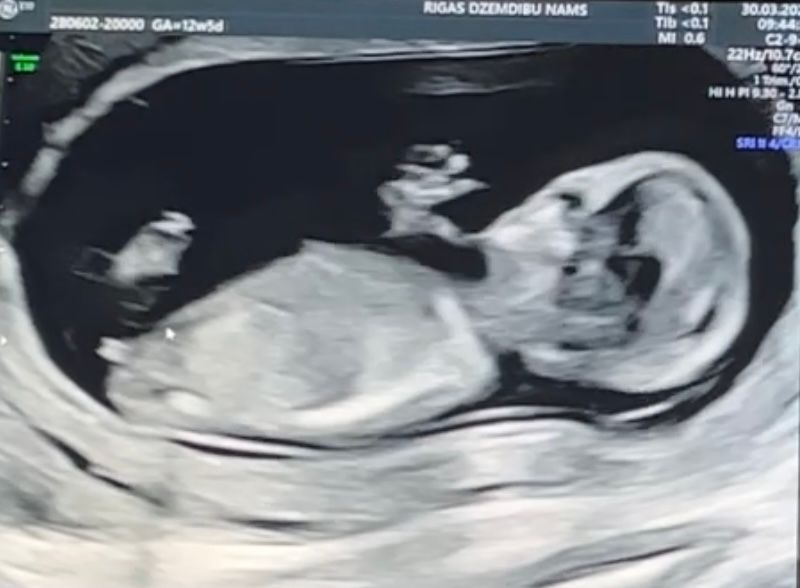

Вчера была на первый скрининг в 12,5 недель. Сказали что пол можно узнать только через 2 месяца. В видео потом увидела этот бугорок, подумала что это яица, но почитала в интернете что это бугорок и можно как то определить будит мальчик или девочка, так вот, что думаете? И кстати у нас сердцебиение 159, читала что у мальчиков обычно ниже. 🤔 Очень хочу девочку😄🥰

Похоже на девочку ,но там ножки видно и пол Богорок вроде параллельно ,но конечно достовернее через месяц